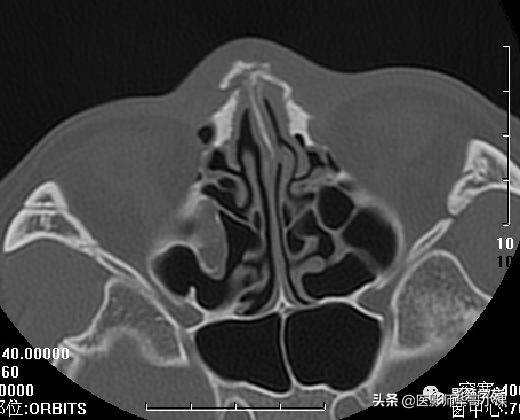

双侧鼻骨骨折

鼻中隔骨折